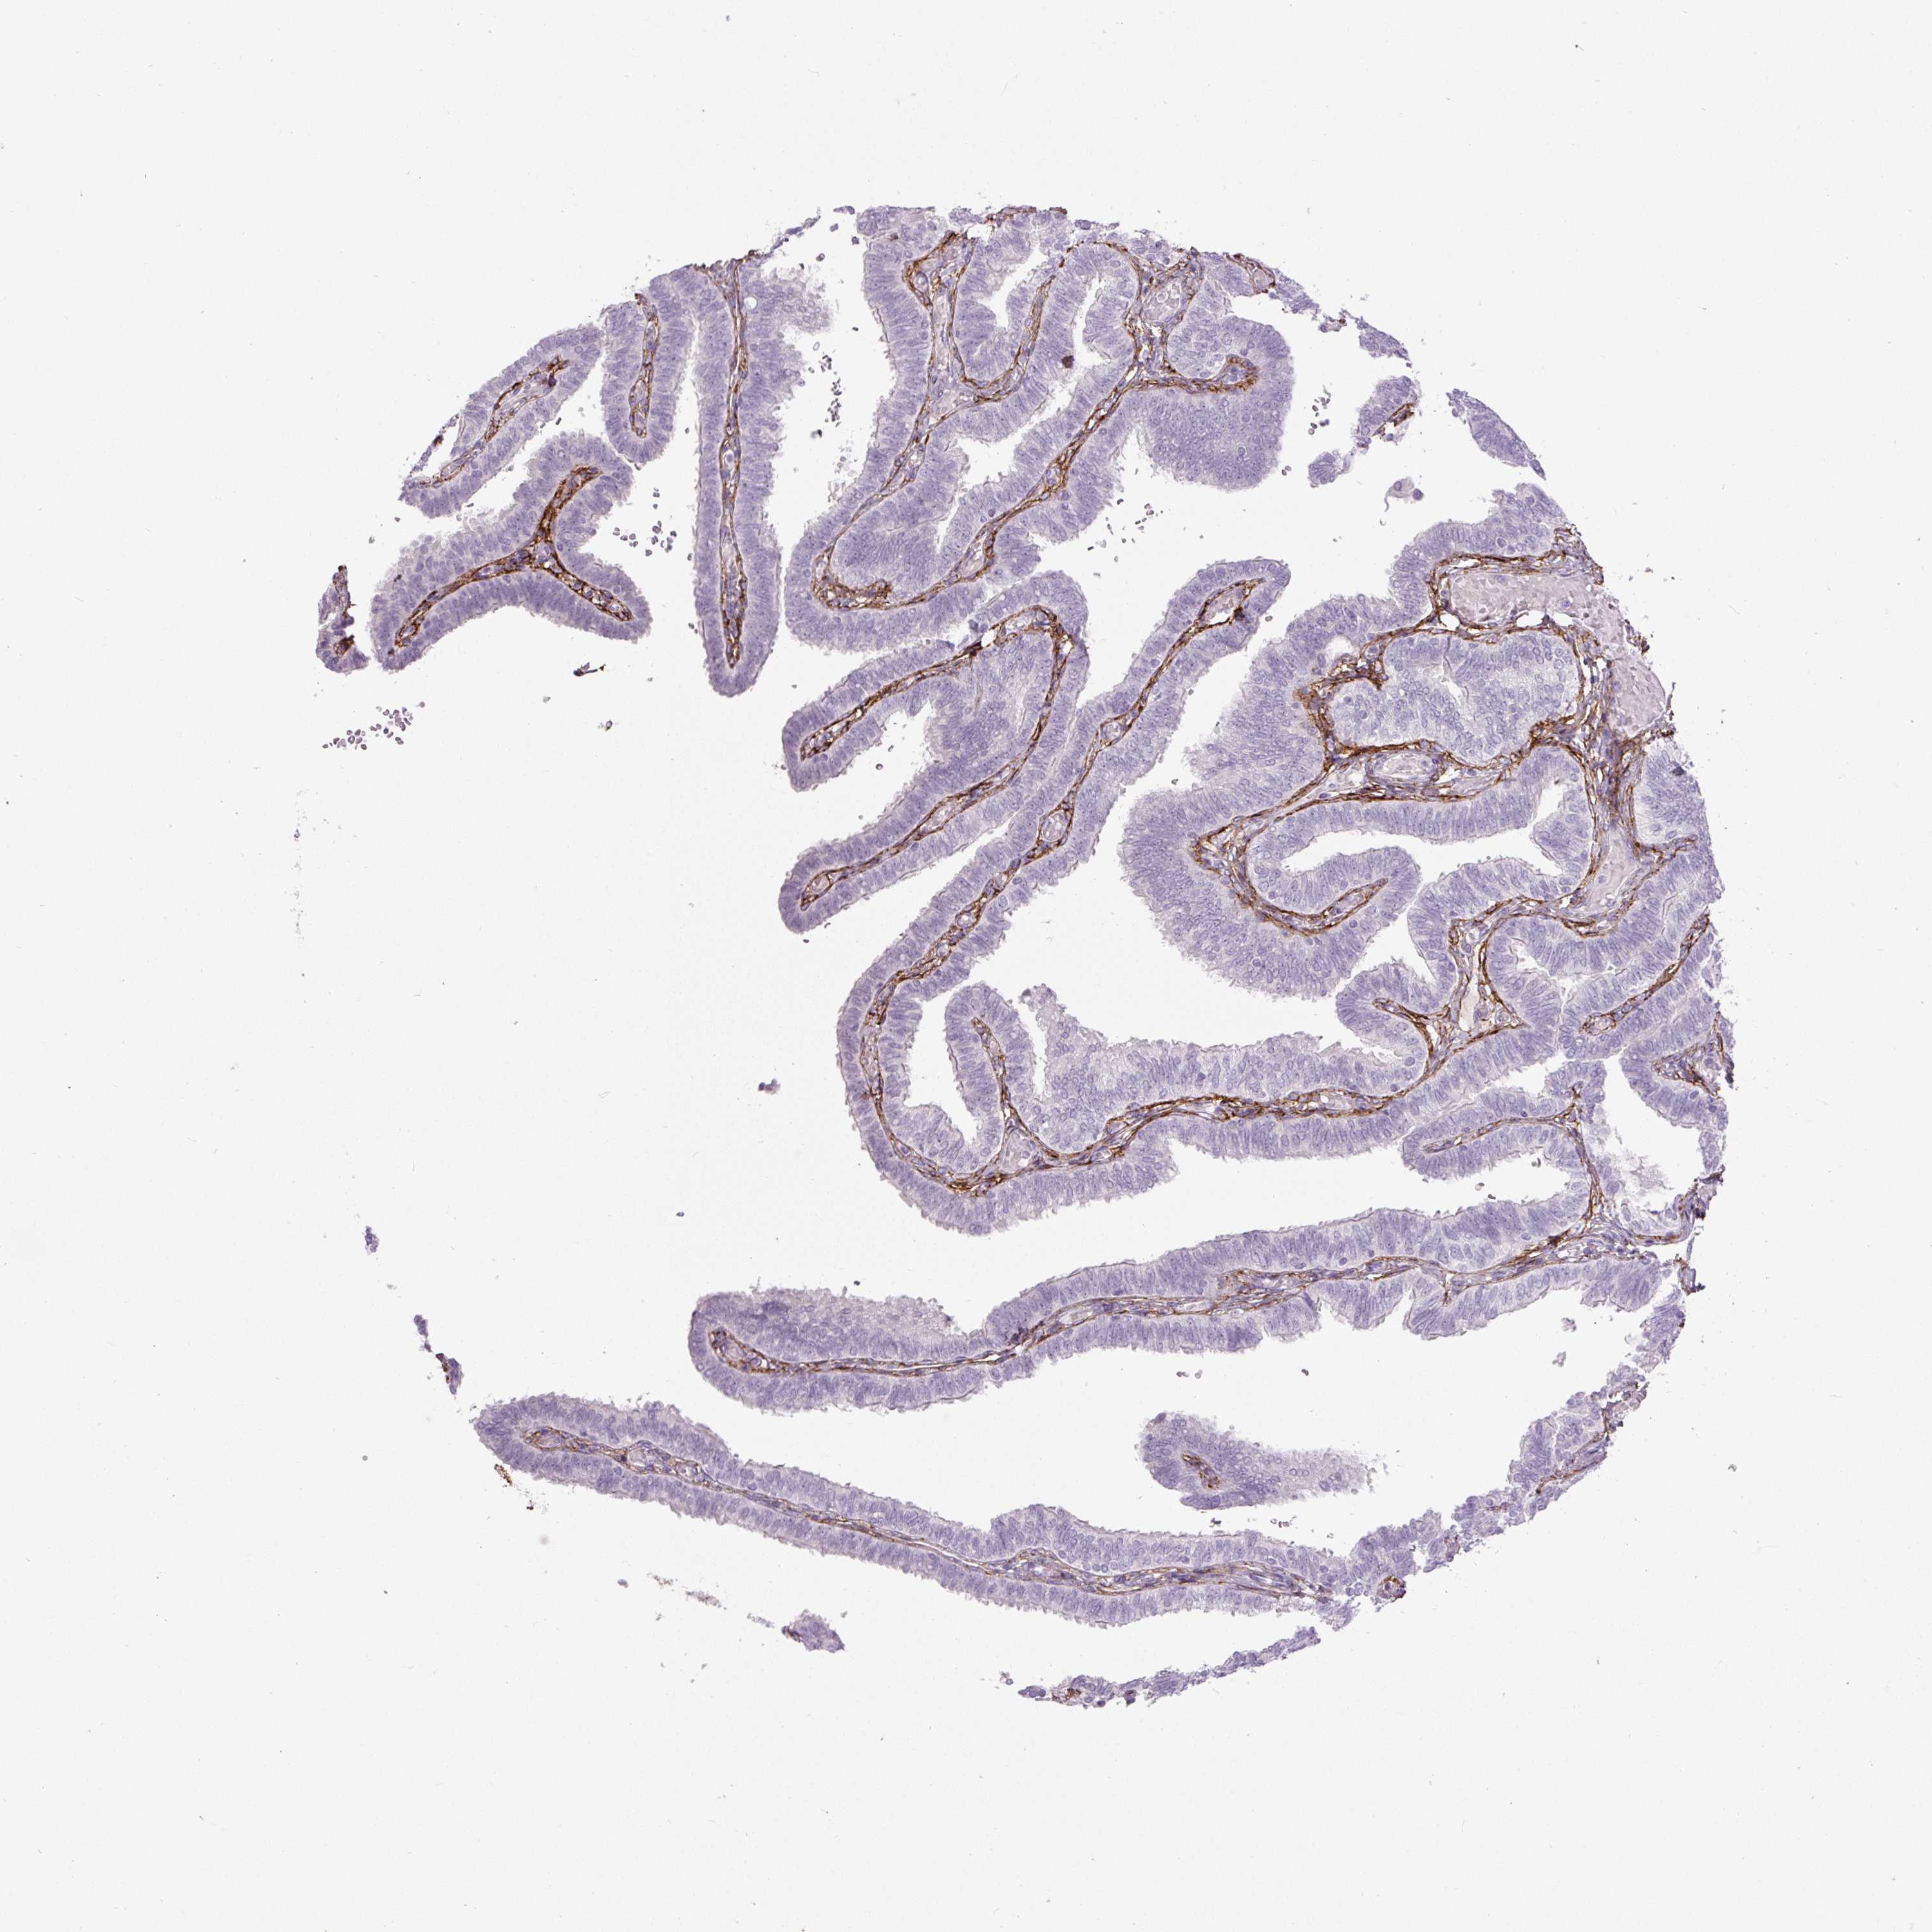

FALLOPIAN TUBE - Antibody stainingi

Antibody staining in the annotated cell types in the current human tissue is reported as not detected, low, medium, or high, based on conventional immunohistochemistry profiling in selected tissues. This score is based on the combination of the staining intensity and fraction of stained cells.

Each image is clickable and will lead to virtual microscopy that enables deeper exploration of all samples and also displays staining intensity scores, fraction scores and subcellular localization as well as patient and tissue information for each sample.

Antibody HPA017759Antibody HPA021057Antibody CAB002670Antibody CAB058696Antibody CAB068188Antibody CAB080202

Glandular cells LowNot detectedNot detectedNot detectedNot detectedNot detected